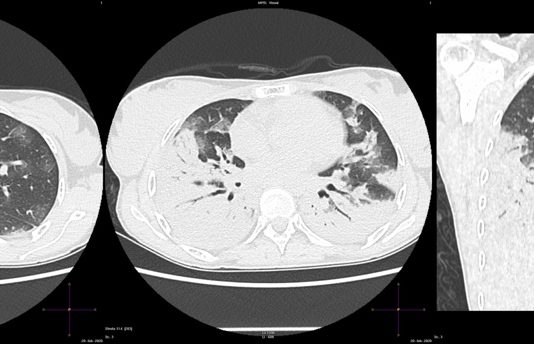

Uomo 43 anni, nessuna comorbidità nota. Febbre e tosse non produttiva. Leucopenia. Insufficienza respiratoria ipossemica e ipocapnica. Contatto con soggetti zona rossa. Tampone positivo NCOV 19.

HRTC Torace

Figura 1